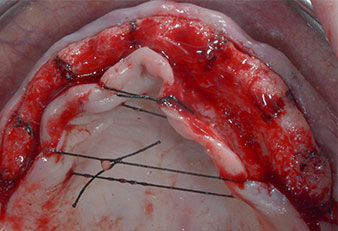

Implant positions

Fig. 2: After mid-crestal incision and preparation of mucoperiosteal flaps the implant positions are transferred to the bone.